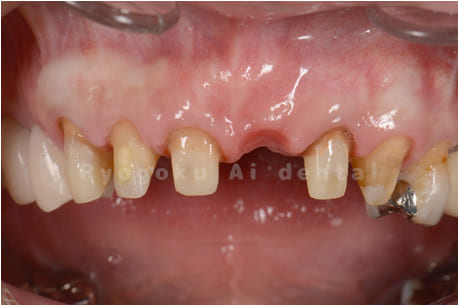

Case01

- 原因

- 重度縁下カリエス

- 治療期間

- 約4ヶ月(最終補綴物装着まで含む)

- 治療内容

- クラウンレングスニング+歯周外科

- 治療費用

- 110,000円(最終補綴を除く)

前歯の虫歯が大きく、3前歯部を含む歯周外科・クラウンレングスニングを行った患者様です。

<リスク・副作用>

手術後は痛み、腫れ、痺れ、青あざなどの副作用が生じます。痛みは痛み止めを処方しますが、腫れ、青あざは1週間程度生じる場合があります。また、部位によっては神経の走行が複雑で、痺れが残り、長期的にお薬を処方する場合があります。